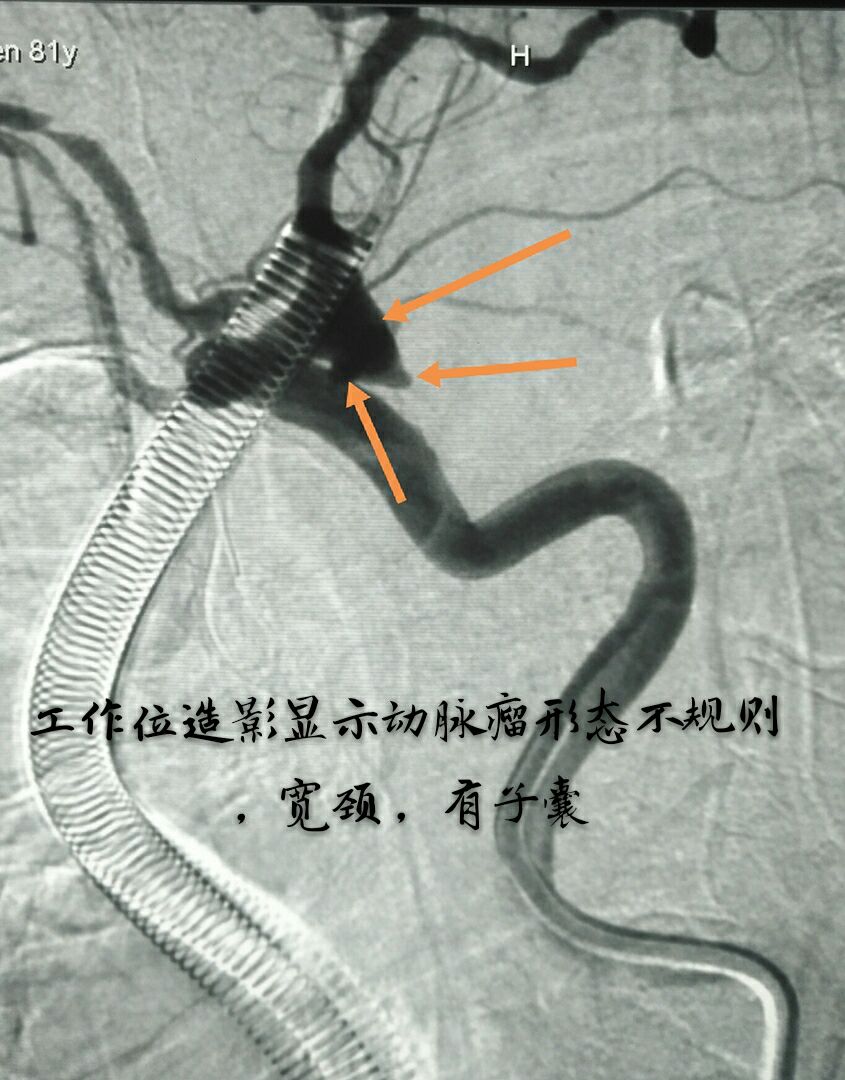

病例三:87岁女性患者,突发头痛、恶心、呕吐,头颅CT示蛛网膜下腔出血量较大,DSA示左侧颈内动脉后交通段动脉瘤,宽颈,形态不规则,有子囊

支架辅助下动脉瘤致密栓塞,因后交通动脉从瘤体发出,并靠近子囊,无法保护,决定牺牲同侧后交通动脉,好在同侧大脑后动脉P1段存在,最终无任何症状体征